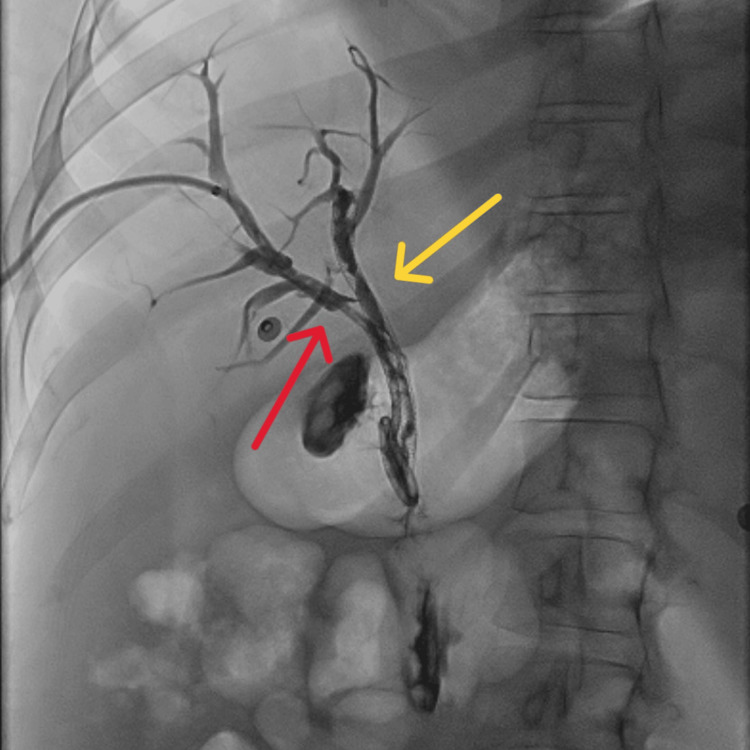

Abdominal computed tomography (CT) with IV contrast showed multiple peripherally enhancing masses within the liver, as well as bilateral intrahepatic biliary ductal dilation (Figure 1). Endoscopic ultrasound revealed multiple large solid masses in the liver consistent with metastases and excluded a fluid component, i.e., abscess. Due to the acute cholangitis, endoscopic retrograde cholangiopancreatography (ERCP) was performed, and the PTC drain was visualized emerging from the major papilla. The common bile duct was then cannulated using a balloon adjacent to the PTC drain, and contrast was injected. The cholangiogram showed a normal CBD and a mild stricture in the common hepatic duct, but the PTC drain was in an entirely separate ductal system (Figure 2A). A metal stent was then placed into the CBD and extended from the common hepatic duct to the major papilla (Figure 2B). The metal stent emerged from the major papilla adjacent to the PTC drain (Figure 3). Due to concern about the misplacement of the PTC drain, the interventional radiology (IR) team interrogated the drain using contrast (Figure 4). This revealed the presence of a DCBD, with the PTC drain placed in the right CBD and an endoscopically placed metal stent in the left CBD. Consecutive images from the contrast study showed a single proximal communication between the two CBDs. The IR team then removed the PTC drain, and a metal stent was placed in the right CBD, with both stents joining at the major papilla, thus confirming the presence of type Vb DCBD (Figure 5). Following the placement of both metal stents, the patient’s serum bilirubin levels normalized, and symptoms improved to where she was safely discharged home to continue her palliative chemotherapy regimen with her oncologist. Upon following up with her oncologist, her serum bilirubin was 1 mg/dL. The patient ultimately elected to pursue home hospice care shortly afterward.

As evidenced by Figure 5, our patient had a type Vb DCBD as there were two separate extrahepatic bile ducts with a single proximal communicating channel that both had common drainage into the duodenum. As mentioned earlier, there are only two other cases of type Vb DCBD reported thus far [ref. 8,ref. 9]. Both cases involved older female patients, 81-years-old and 44-years-old, respectively, who both presented with cholangitis due to choledocholithiasis [ref. 8,ref. 9], unlike our case where she presented with cholangitis due to cholangiocarcinoma causing biliary obstruction.